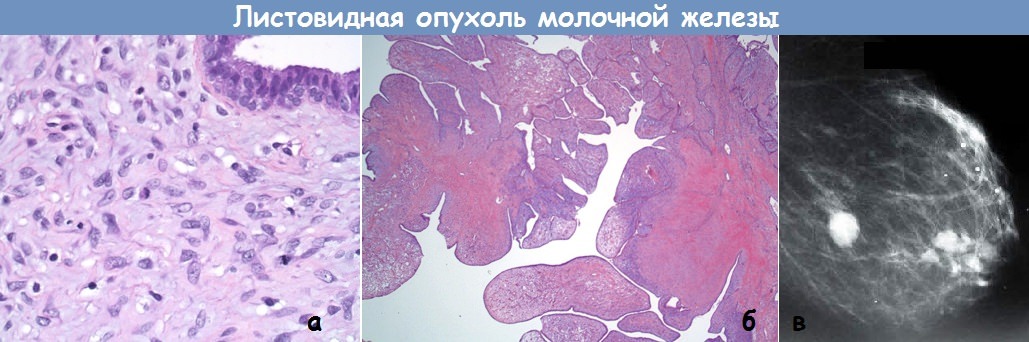

Фотографии опухоли медуллярной аденокарциномы

Раздел: Снимки-откровения